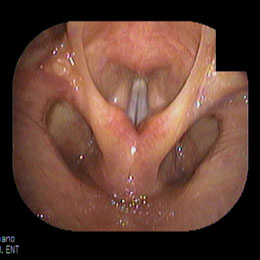

正常な声帯 発声時

当院における内視鏡診療の中核をなすのがこの電子ファイバースコープです。 鼓膜や鼻の奥、のどの観察は耳鼻咽喉科にとって欠かせないものですが、当院では原則として鼓膜の観察は、この電子ファイバースコープを用いておこなっています。 ファイバーと呼ばれるだけあって、柔らかい素材でできており、細く曲がったところもスルスルと通り抜けて目的の場所をくっきりと映し出してくれます。 耳の中(外耳道)や鼻の中がまっすぐな人はいません。電子ファイバースコープはクネクネ曲がりますので、耳、鼻、のどの観察にもってこいです。当院の電子ファイバースコープは直径2.6mmと世界でも細径クラスです。

電子ファイバースコープを用いることによって「裸眼もより正確な診断ができる」ことと、患者様にも鼓膜の状態をご覧いただけて、その画像を時系列で保存し閲覧ができるため、患部の状態の経過(良くなってきているのか、悪化しているのか?)が一目瞭然でご確認いただけます。